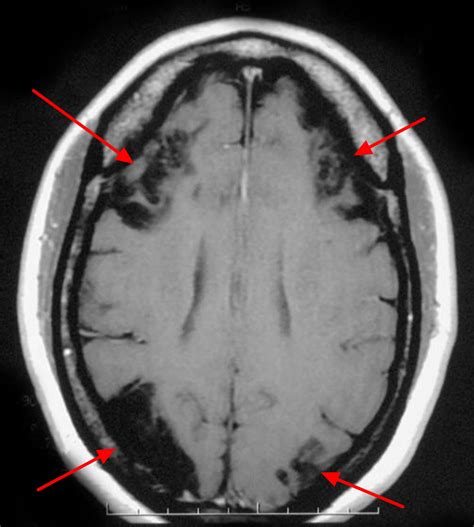

A Watershed Brain Infarct is a specific and critical type of ischemic stroke that occurs in the border zone areas of the brain. Unlike typical strokes that are caused by a blockage in a major artery, these infarctions happen in the "watershed" regions—the most distal areas of blood supply where the territories of two major cerebral arteries meet. Because these areas are the farthest from the heart and rely on the delicate balance of pressure from multiple sources, they are exceptionally vulnerable to drops in systemic blood pressure and reduced blood flow.

• Cortical Watershed Infarct: Located at the borders between the anterior, middle, and posterior cerebral artery territories on the surface of the brain.

• Internal Watershed Infarct: Located in the white matter deep within the brain, often at the border between the deep and superficial arterial systems.

The symptoms of a Watershed Brain Infarct often manifest based on the location of the injury. Patients might experience "man-in-the-barrel" syndrome, where the shoulders and upper arms are weaker than the hands and legs. Other signs include cognitive impairment, language difficulties, or visual field deficits.